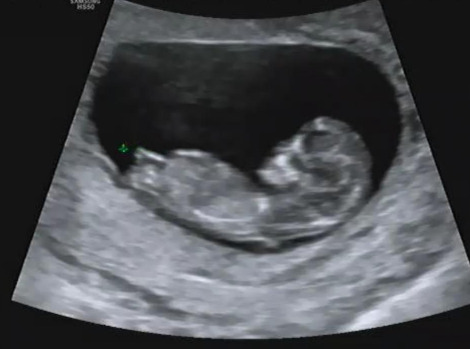

Screenshot_20190521-164322.jpg 11주 1일 차 초음파